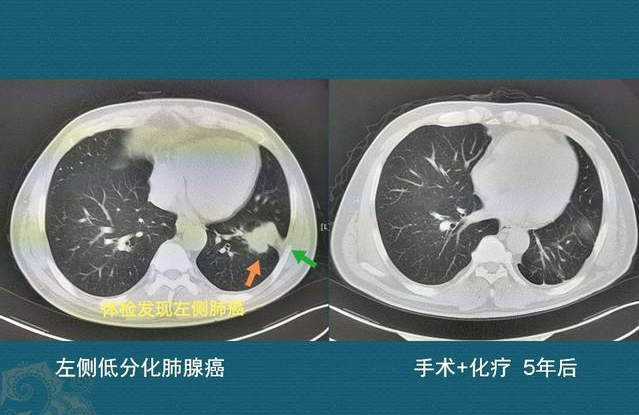

周围型肺癌案例

这是一位53岁男子,不吸烟,因为咳嗽、胸痛查出左下肺分叶状肿块(4.5×4.0cm),伴有胸膜牵拉,肿瘤靠近肺门一侧还有一颗肿大淋巴结,恶性征象很明显,选择直接手术切除,病理是腺鳞癌,低分化:

他的免疫组化:p63+,CK5/6+(少数),Syn-,CgA-,虽然是低分化,比较幸运的是清扫11颗纵隔及肺门淋巴结,均未发现癌细胞转移,术后做了规范的化疗,5年后复查恢复很好,没有复发!这个病例告诉我们:周围型肺癌,有机会治愈!